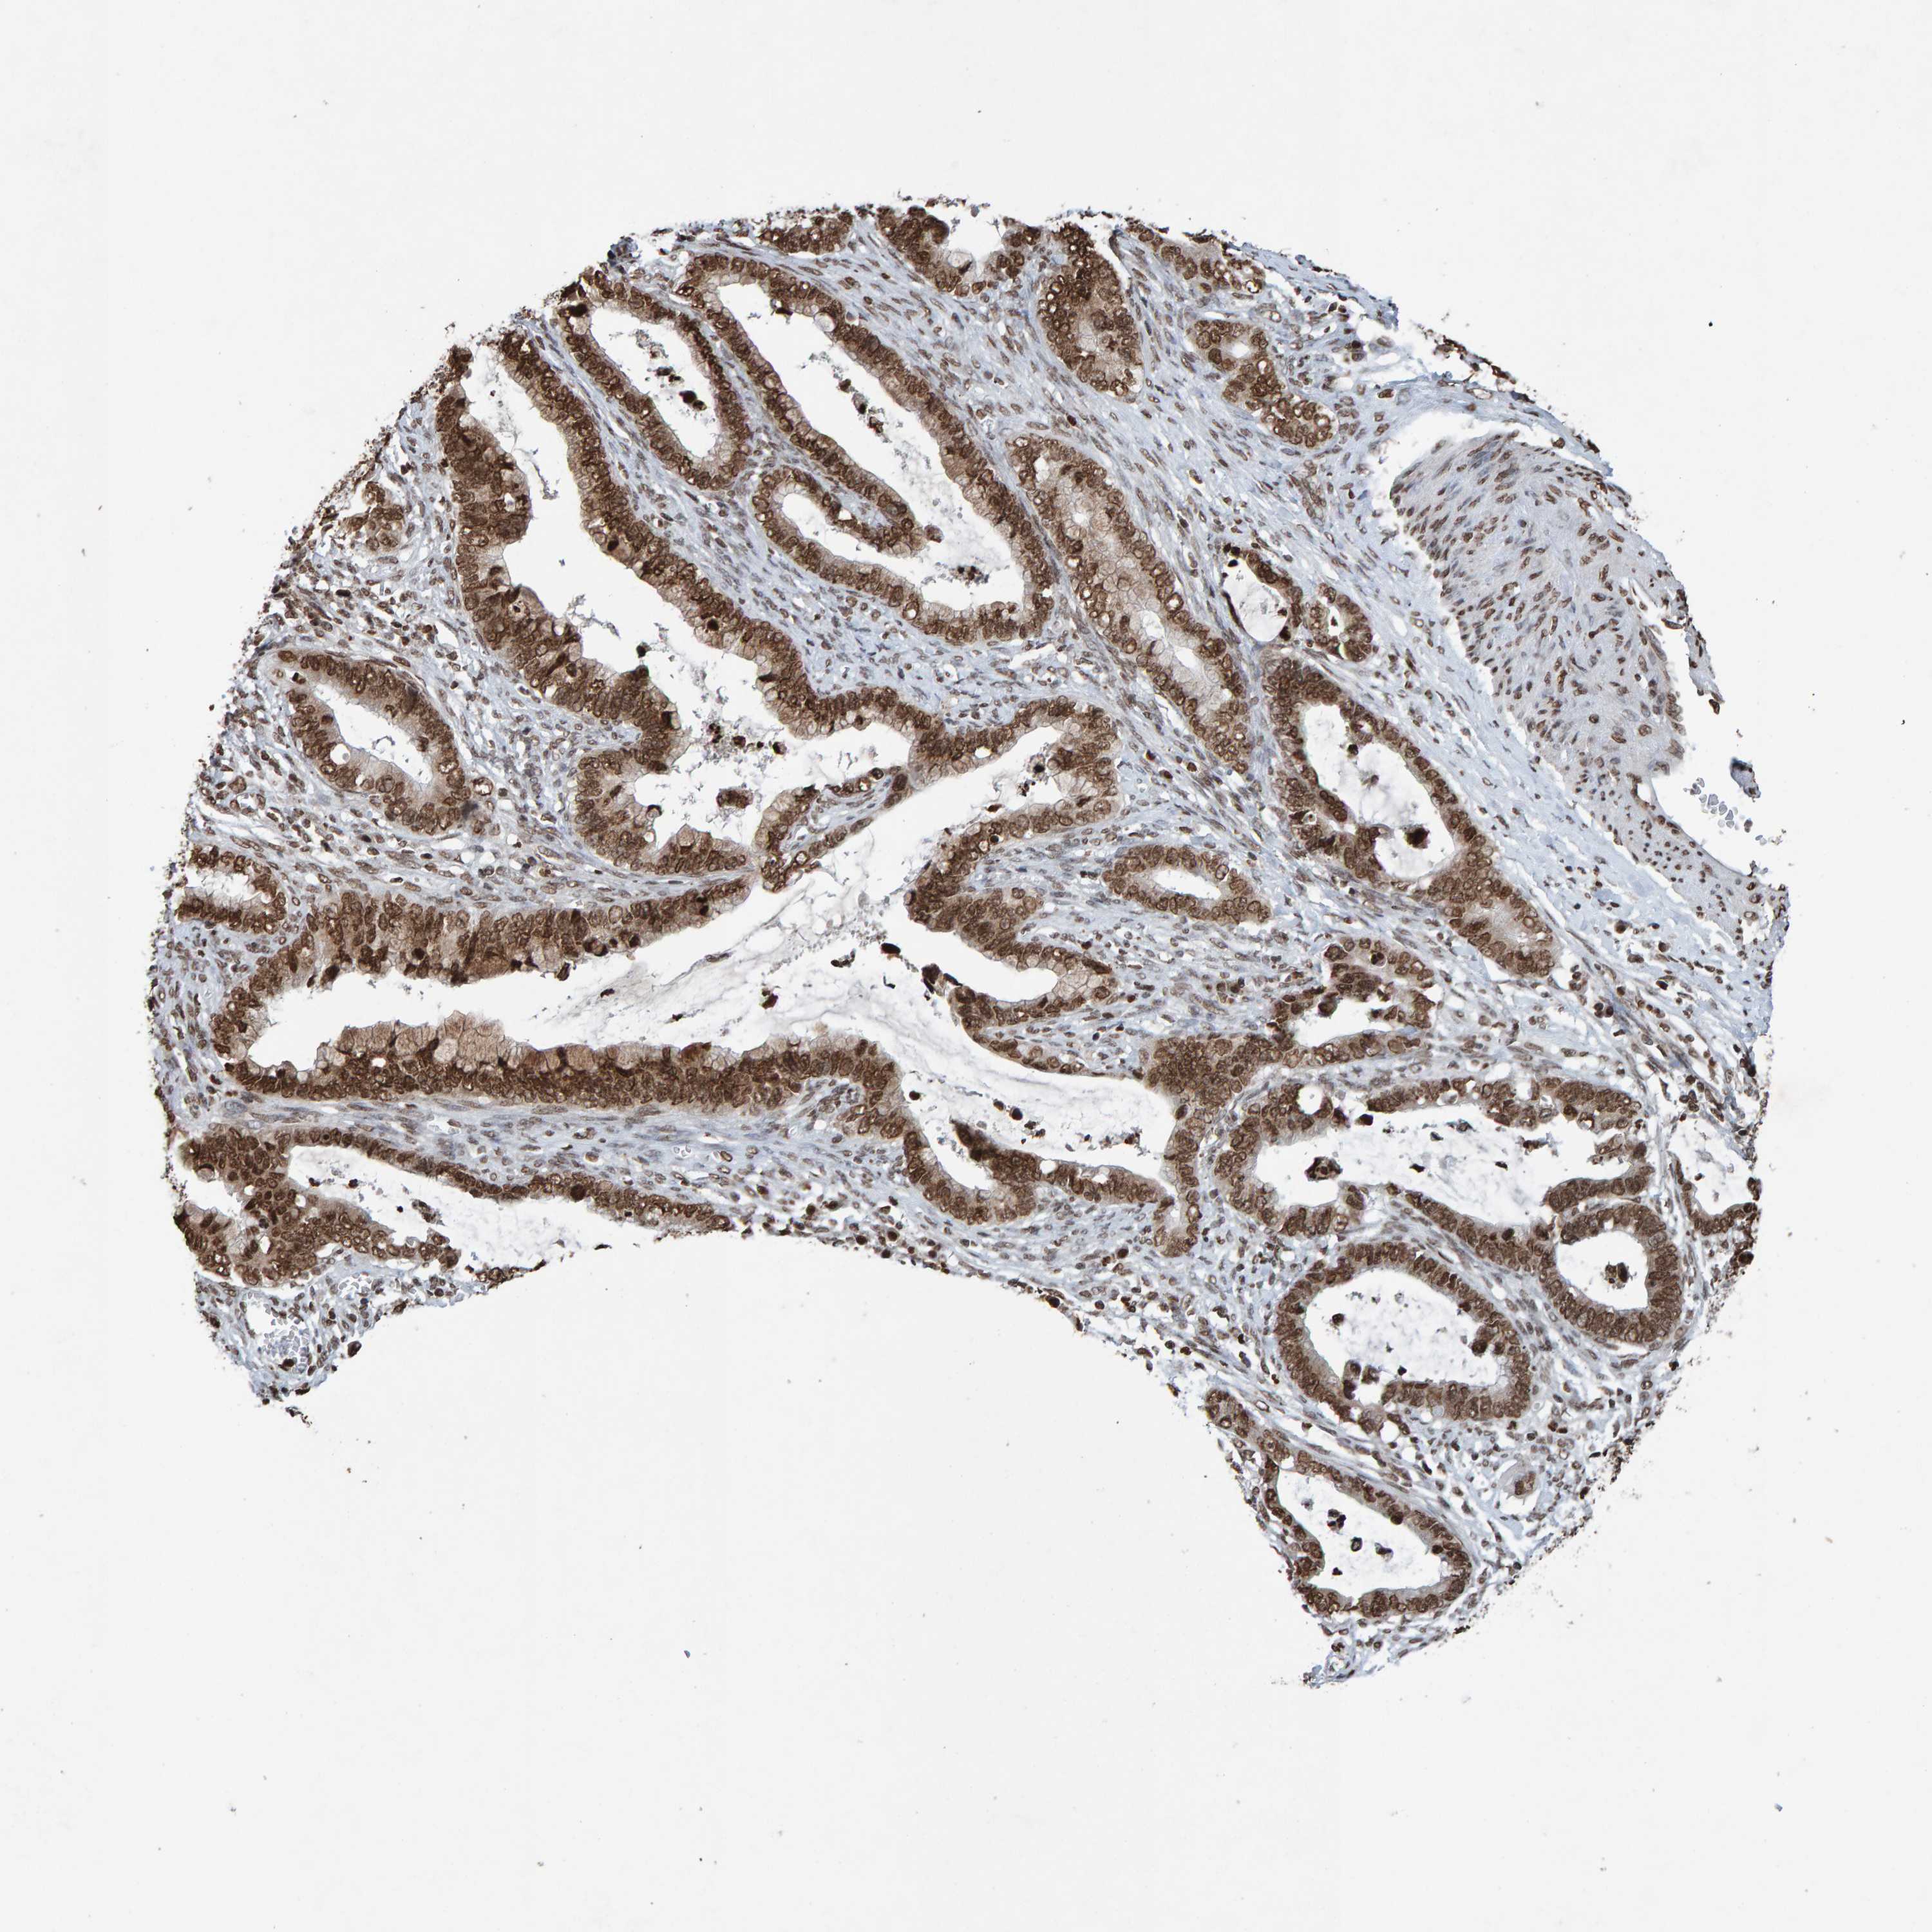

CERVICAL CANCER - Protein expressioni

A mouse-over function shows sample information and annotation data. Click on an image to view it in a full screen mode. Samples can be filtered based on level of antibody staining by selecting one or several of the following categories: high, medium, low and not detected. The assay and annotation is described here.

Note that samples used for immunohistochemistry by the Human Protein Atlas do not correspond to samples in the TCGA dataset.

Antibody stainingi

Antibody staining in the annotated cell types in the current human tissue is reported as not detected, low, medium, or high, based on conventional immunohistochemistry profiling in selected tissues. This score is based on the combination of the staining intensity and fraction of stained cells.

Each image is clickable and will lead to virtual microscopy that enables deeper exploration of all samples and also displays staining intensity scores, fraction scores and subcellular localization as well as patient and tissue information for each sample.

Antibody HPA057236

Antibody CAB022549

Staining

High

Medium

Low

Not detected

Intensity

Strong

Moderate

Weak

Negative

Quantity

>75%

75%-25%

<25%

None

Location

Nuclear

Cytoplasmic/membranous

Cytoplasmic/membranous,nuclear

Squamous cell carcinoma, NOS

Adenocarcinoma, NOS